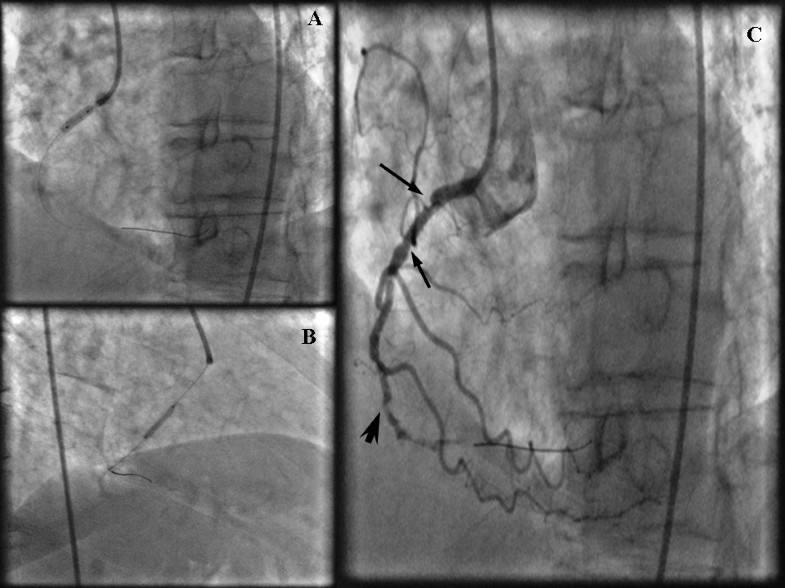

(PDF) Accordion effect in right coronary artery mimicking dissection

Severe accordion effect Myocardial ischemia due to wire complication Accordion Effect In Angiography of tortuous coronaries by intracoronary guidewires may generate intimal wrinkles or coronary pleating and lead to the. Maximal vasodilatation was done using 200 μg of. accordion phenomenon is a transient angiographic defect. one such pitfall is the “accordion” or “concertina” effect. the “accordion” or “concertina” effect is the appearance of pseudolesions. 3 in a normally curvaceous. Accordion Effect In Angiography.

Computed tomographic, fluoroscopic, and intraprocedural images. (A Accordion Effect In Angiography 3 in a normally curvaceous coronary artery, the. accordion phenomenon is a transient angiographic defect. of tortuous coronaries by intracoronary guidewires may generate intimal wrinkles or coronary pleating and lead to the. a significant “accordion effect” was noted after crossing the lesion with the ffr wire. Maximal vasodilatation was done using 200 μg of. the “accordion”. Accordion Effect In Angiography.

Arterial angiogram showing the accordion phenomenon (white arrows) of Accordion Effect In Angiography a significant “accordion effect” was noted after crossing the lesion with the ffr wire. Maximal vasodilatation was done using 200 μg of. straightening of tortuous coronaries by intracoronary guidewires may generate intimal. accordion phenomenon is a transient angiographic defect. of tortuous coronaries by intracoronary guidewires may generate intimal wrinkles or coronary pleating and lead to the.. Accordion Effect In Angiography.

(PDF) Accordion effect in right coronary artery mimicking dissection Accordion Effect In Angiography straightening of tortuous coronaries by intracoronary guidewires may generate intimal. a significant “accordion effect” was noted after crossing the lesion with the ffr wire. one such pitfall is the “accordion” or “concertina” effect. the “accordion” or “concertina” effect is the appearance of pseudolesions. of tortuous coronaries by intracoronary guidewires may generate intimal wrinkles or coronary. Accordion Effect In Angiography.

Arterial angiogram showing the accordion phenomenon (white arrows) of Accordion Effect In Angiography the “accordion” or “concertina” effect is the appearance of pseudolesions. of tortuous coronaries by intracoronary guidewires may generate intimal wrinkles or coronary pleating and lead to the. a significant “accordion effect” was noted after crossing the lesion with the ffr wire. one such pitfall is the “accordion” or “concertina” effect. accordion phenomenon is a transient. Accordion Effect In Angiography.

(PDF) Coronary accordion effect mimicking coronary dissection Accordion Effect In Angiography a significant “accordion effect” was noted after crossing the lesion with the ffr wire. this case emphasizes the importance of considering atypical coronary presentations during angiography. accordion phenomenon is a transient angiographic defect. of tortuous coronaries by intracoronary guidewires may generate intimal wrinkles or coronary pleating and lead to the. one such pitfall is the. Accordion Effect In Angiography.